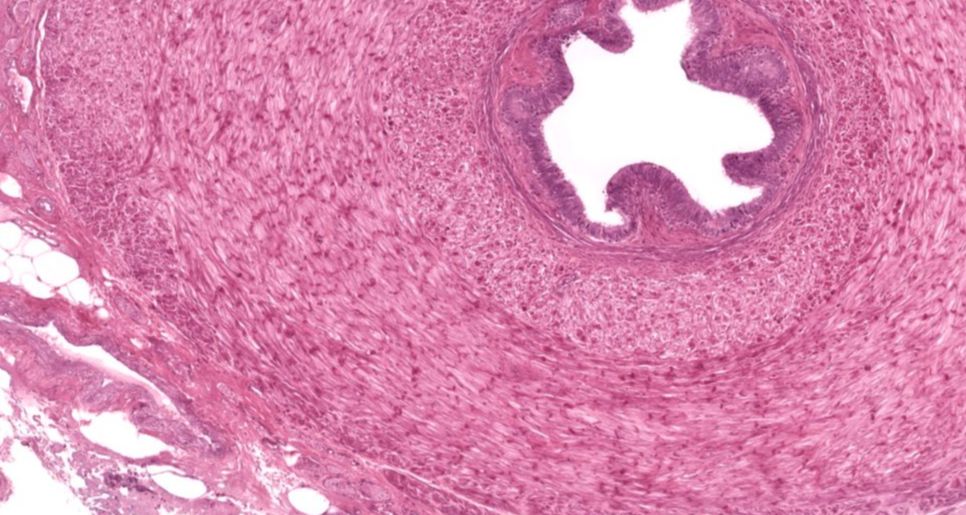

Ureter